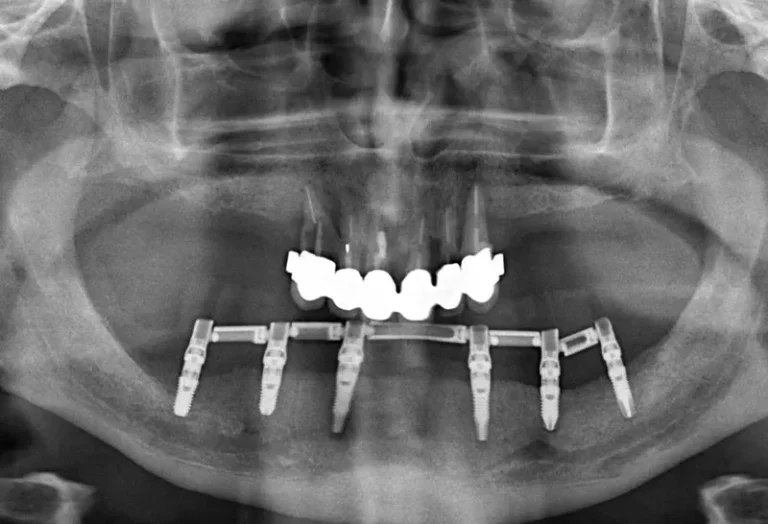

La osteointegración es el proceso biológico fundamental que determina el éxito de los implantes dentales. Durante este fenómeno, el hueso del maxilar crece y se fusiona directamente con la superficie del implante de titanio, creando una conexión estructural y funcional que garantiza la estabilidad a largo plazo. Este proceso, descubierto por el profesor Per-Ingvar Brånemark…

La regeneración ósea es un procedimiento quirúrgico fundamental en implantología dental que permite recuperar el volumen y la densidad del hueso maxilar o mandibular cuando este se ha perdido. Este tratamiento se vuelve necesario cuando el paciente no dispone de suficiente tejido óseo para sostener un implante dental de manera segura y estable. Mediante el…